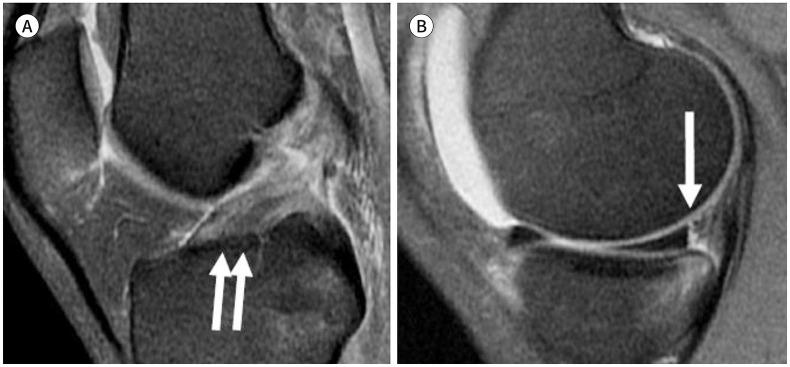

To accurately interpret knee MRI, it is important not only to know the basic meniscal anatomy but also to distinguish it from that under pathological conditions. Thus, it would be helpful to know the normal meniscus variants (false positives) that could be mistaken for meniscal tears, and tears that could easily be missed and incorrectly diagnosed as normal (false negatives). False positives include synovial recesses, meniscal flounce, the relationship between the popliteus tendon and lateral meniscus, transverse ligament, the anterior root of the meniscus, and meniscofemoral ligament. False negatives include focal radial tears, flap tears, posterior root tears, meniscocapsular separation, and discoid meniscal tears. In this pictorial essay, we reviewed the imaging data obtained in the aforementioned cases.